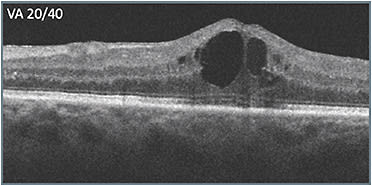

Unfortunately, the patient was unable to return for 10 weeks. When she did return, (C) her vision had worsened dramatically (20/150). In deciding what to do, the apparent progression of disease signs that had occurred over time (B & C) were considered. Retinal layer disorganization progressed, including what appeared to be signs of DRIL. More hyperreflective foci appeared as well, presumably indicating accumulation of exudate, including near the fovea. The decision was made to switch to a different class of therapy, which produced a favorable response (D). Vision improved from 20/150 to 20/60, and the retinal anatomy appeared as intact as it had been during the course of treatment.

The patient’s macular edema continues to be active, but with the regimented treatment, her status has been stable. While 20/60 visual acuity (VA) was an improvement, it’s not optimal, which raises the question of whether switching to a different treatment class sooner may have helped prevent progression to retinal layer disruption.